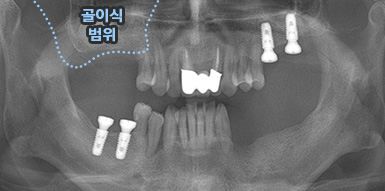

치조골이식술

임플란트의 성공률 UP!

골이식 임플란트

치조골 이식술이란?

치주염 등으로 치조골(잇몸뼈)의 양이 부족한 경우

치조골 이식술을 통하여 충분한 뼈의 양을 확보한 후

임플란트를 식립합니다.

뼈의 밀도가 치밀하고 단단하며, 양이 충분할수록 임플란트의 성공률이 높아집니다.

청담네오플란트는 풍부한 경험의 의료진이 치조골 이식술을 통해 치조골을 적절한 양과

밀도로 재생시킨 후 임플란트를 식립합니다. 뼈의 흡수가 심하지 않아 적은 양의

치조골 이식을 하는 경우 임플란트 식립을 동시에 진행할 수 있지만, 뼈의 흡수가

심하여 많은 양의 치조골 이식이 필요한 경우 치조골 이식술을 먼저 진행한 후,

치조골이 재생되면 임플란트를 식립하여 보다 정밀하고 안전한 시술 결과를 얻을 수 있습니다.